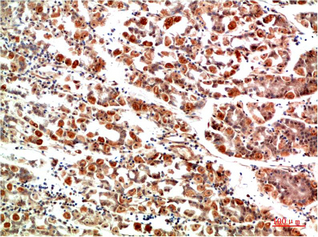

Applications :WB, IHC

| Recommended dilutions: | WB 1:500-2,000 IHC 1:50-300 |

| Specificity: | The antibody detects endogenous IkB α protein |